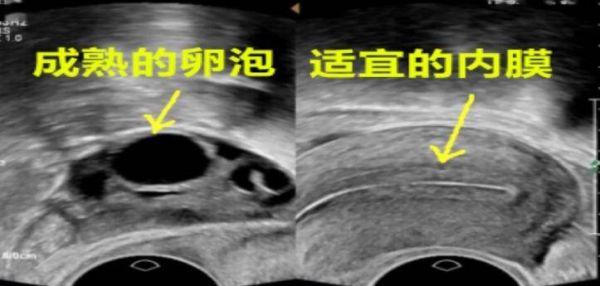

生殖科医生在做B超的时候,可以准确的知道您此时卵泡发育的大小、形态和位置,以及内膜的厚度和形态。随着时间的推移,卵泡会长大成熟,在排卵前卵泡成熟约18-24mm,最大不应超过28mm,排卵后卵泡消失,当最大的卵泡消失时,提示发生排卵。生殖科医师会根据卵泡发育的情况,建议宝子们在最合适的时候安排同房。同房后需择日返院查看卵泡是否已经排了。这样科学的监测方法才不会错过排卵哦~